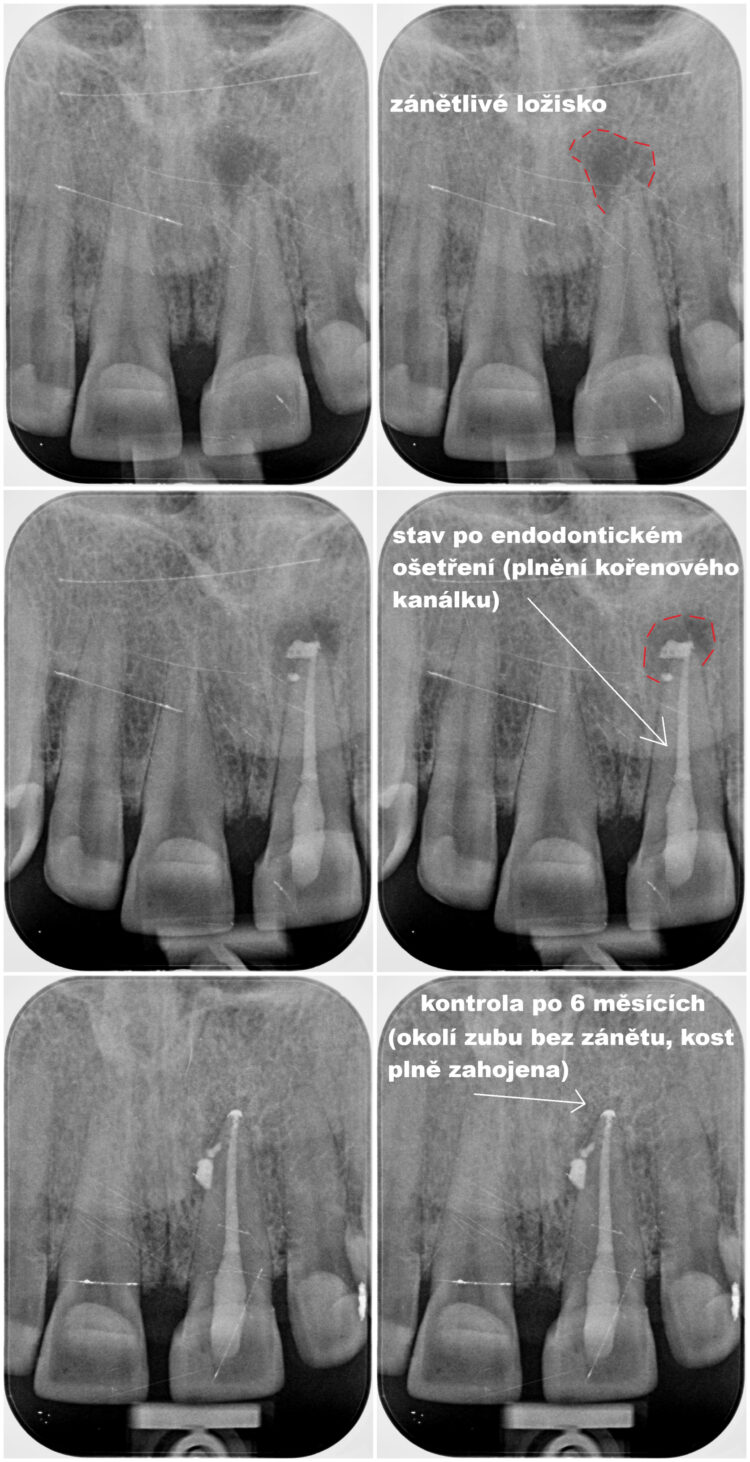

Mikroskopická endodoncie / reendodoncie

Primární nebo sekundární ošetření kořenových kanálků za pomoci operačního mikroskopu.